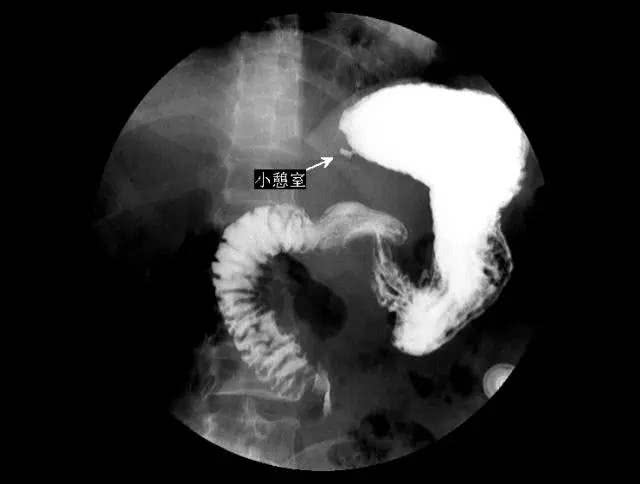

【国宇科普】胃肠疾病除了做胃镜,上消化道钡餐造影也是一种选择!